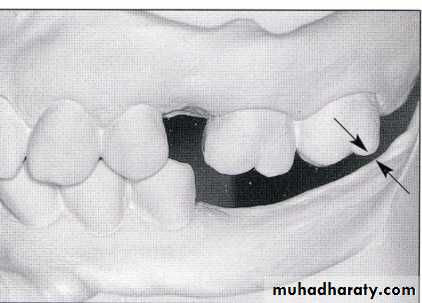

Traumatic vertical overlap

Clinical symptoms of traumatic vertical overlap

AbrasionMobility

Migration of the teeth

Inflammation , ulceration of the gingiva and palatal mucosa

Early recognition of problems and treatment with orthodontic or combined orthodontic and orthognathic surgical procedures are the treatment of choice